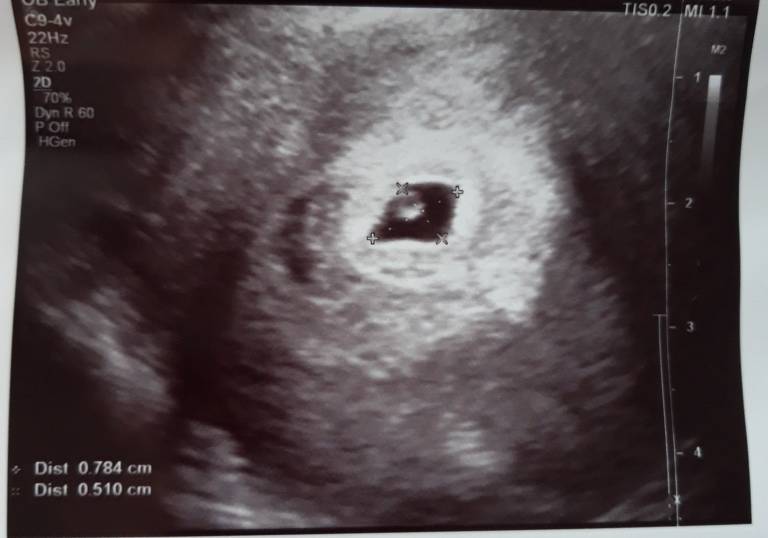

Cudny widokDziewczyny wczoraj byłam na wizycie u gina po receptę na duphaston ale zrobił mi usg z om 5+1 jest zarodek dobrze umiejscowiony no i kolejna wizyta za tydzień jak to powiedział serduszkowa. Tak wam powiem że pierwszy raz byłam u niego prywatnie zawsze na nfz i nie mogę uwierzyć za wizytę z usg zapłaciłam 50 szok że tak mało bo u innych płaciłem 150-200.

A oto moja kruszynka[emoji7] Zobacz załącznik 909345